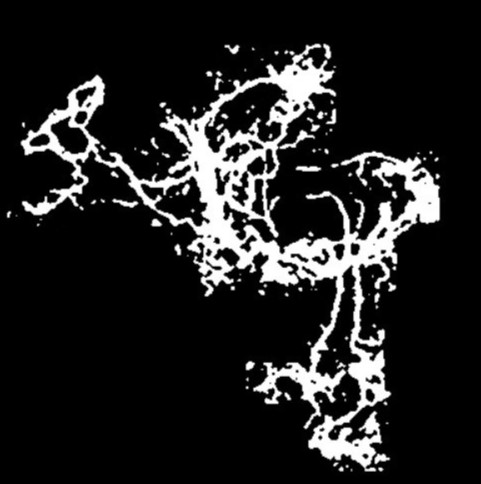

Knowing that an OCTA image has a scale of and that each OCTA image contains pixels, we find the size of one pixel to be 0.154 . The original image after the ”Image Processing” phase focuses on the blood vessel area, represented by the white pixels. It indicates the size of the active mCNV lesion. The internal black areas show parts of the object where the blood vessel is missing. Figure 8 illustrates a structure similar to a sponge.

To calculate the total area, we need to pass the output image from the ”Image Processing” phase through another operation, Region Fill, to fill in the black missing sections from the initial binary image. After applying this filter, the total vessel area will be larger than the mCNV area: .

Feature combination is then applied to compute the Vessel Density, which is the ratio of the mCNV Area to the Total Area: .

Fig. 10 presents the image processing techniques and their outcomes at each iteration. The grayscale images progressively approach a binary representation, as seen after the application of multiple binarization techniques. The salt and pepper filter removes part of the noise. In the final image, all components are colored in a way that highlights the principal component. Any remaining noise is removed in Fig. 11, which also shows the result after applying region filling techniques.